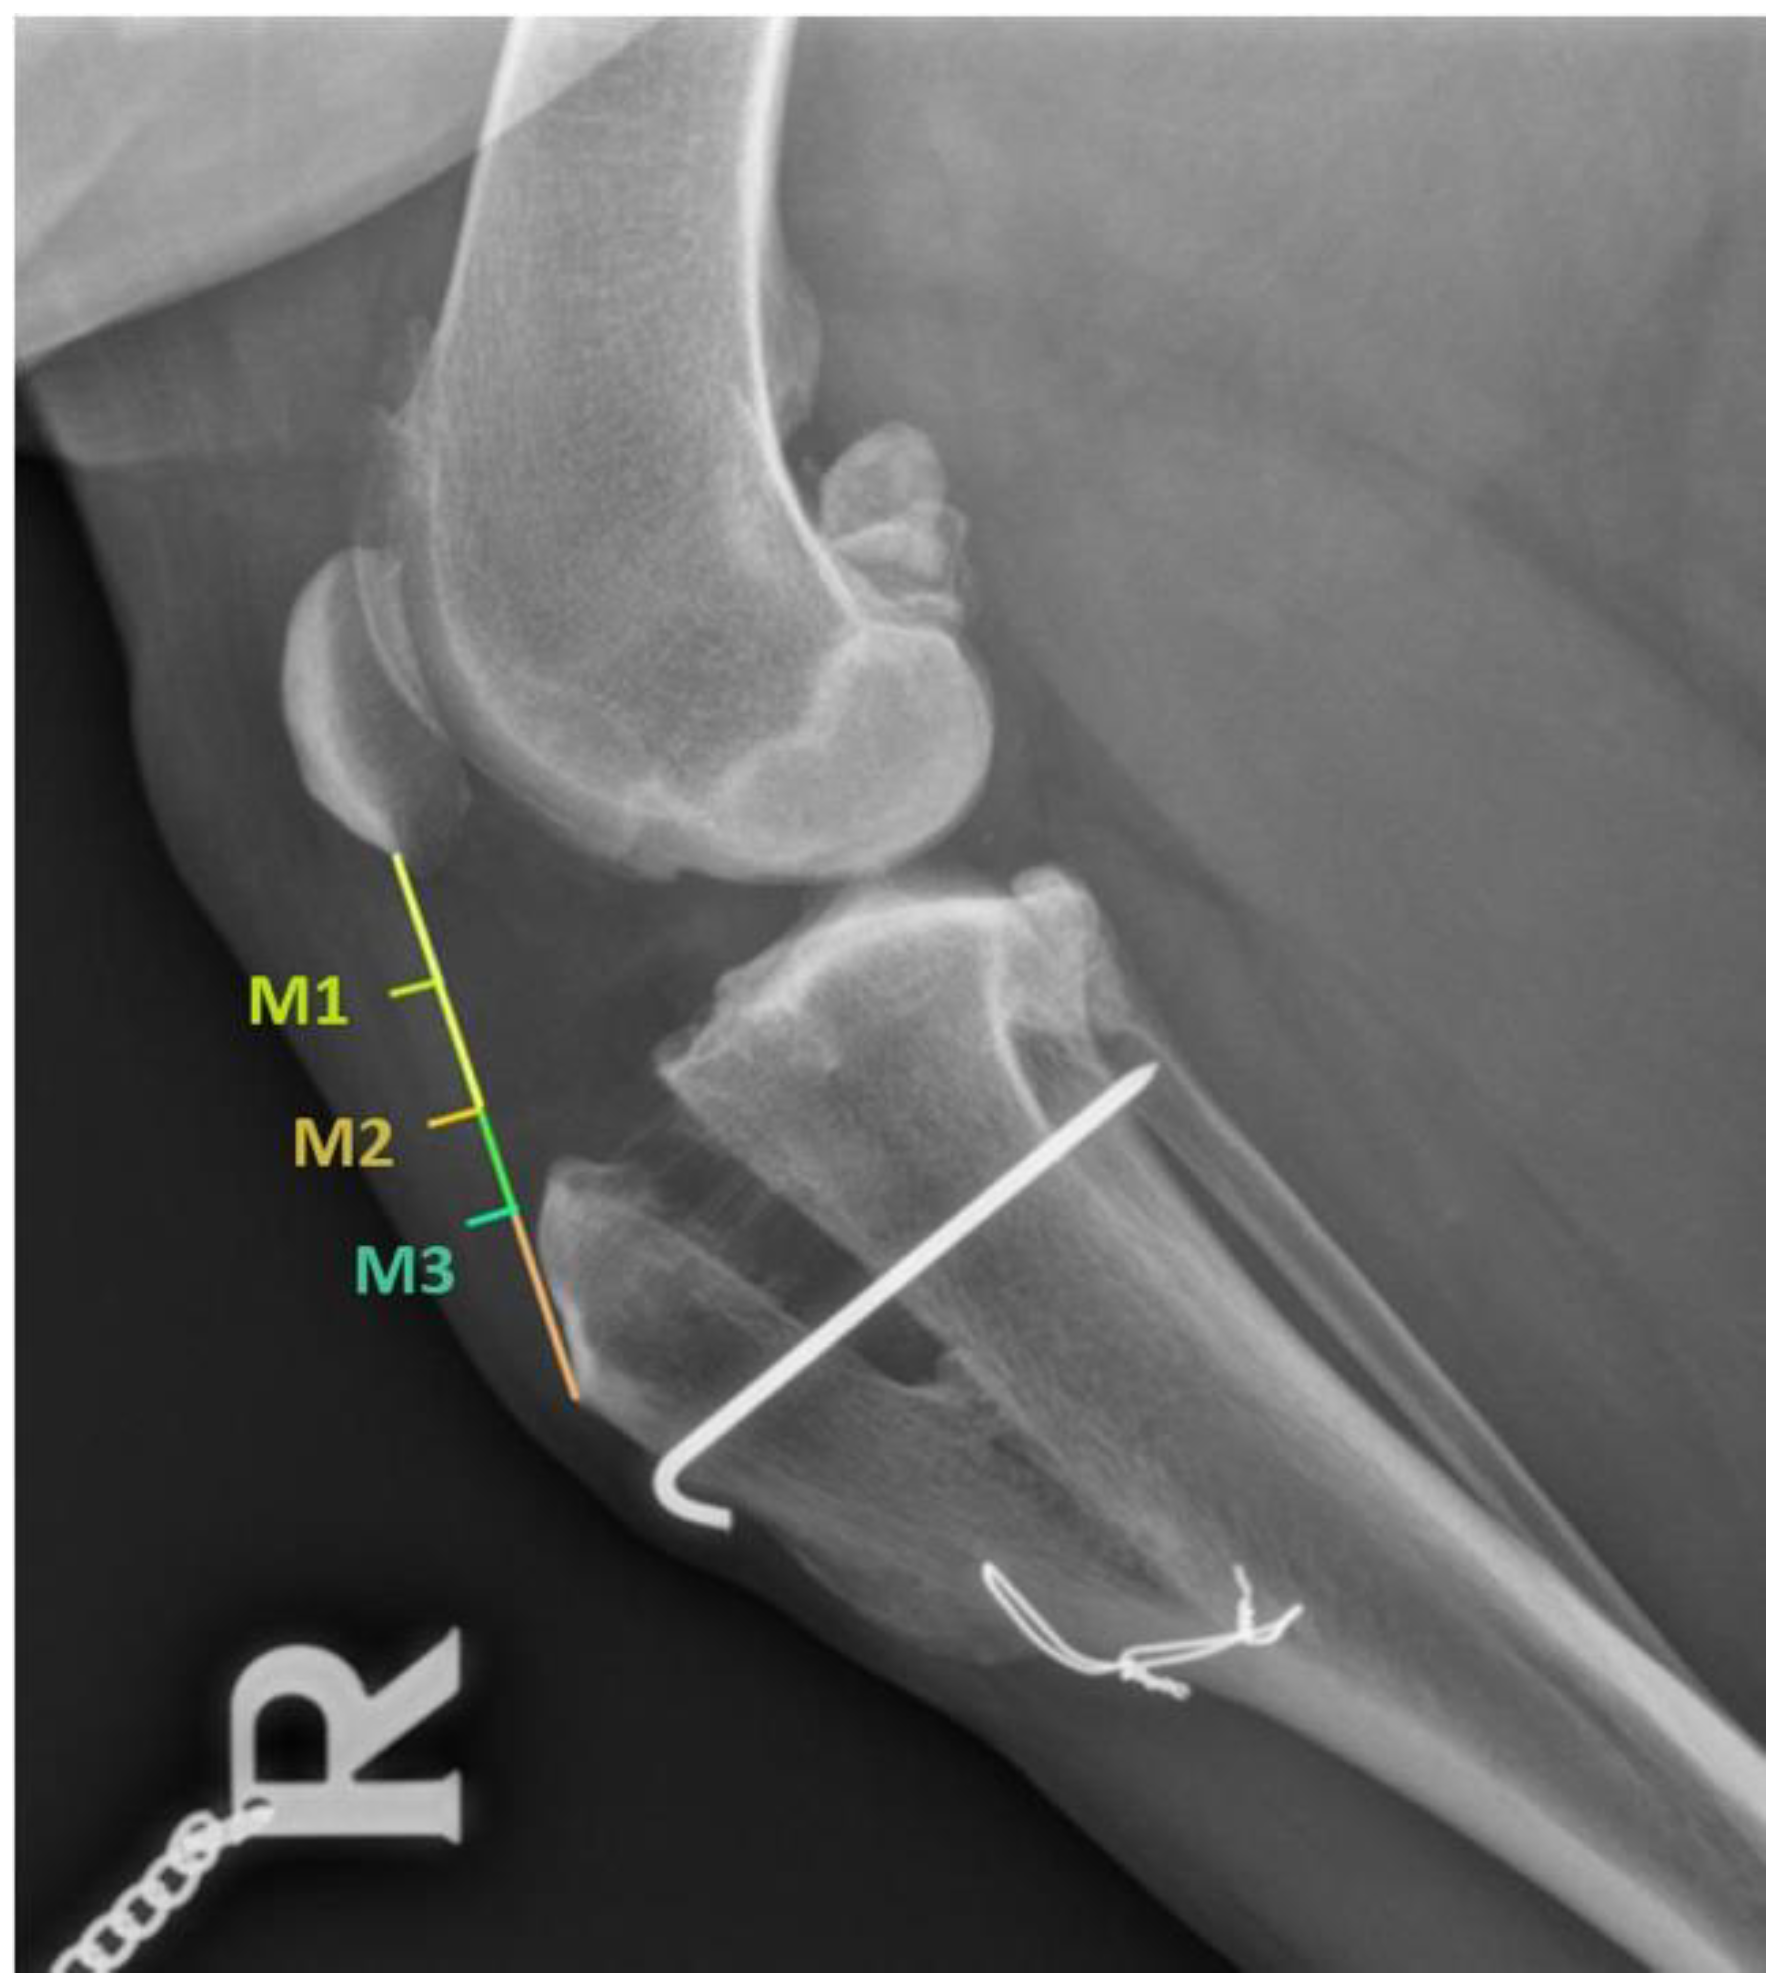

| M-1 | M-2 | M-3 | M-1 | M-2 | M-3 | M-1 | M-2 | M-3 | M-1 | M-2 | M-3 | |

| 2.88 ± 0.73 | 2.84 ± 0.78 | 2.99 ± 0.81 | 4.77 ± 2.48 | 5.21 ± 2.50 | 5.31 ± 2.68 | 3.31 ± 1.48 | 3.88 ± 1.74 | 4.46 ± 1.83 | 3.15 ± 1.42 | 3.50 ± 1.58 | 4.11 ± 2.21 | |

| Mean | 2.90 | 5.09 | 3.88 | 3.58 | ||||||||

| PRGF GROUP (n = 18) (mm) | ||||||||||||

| Pre-surgery (T-0) | First follow-up (T-1) | Second follow-up (T-2) | Third follow-up (T-3) | |||||||||

| 2.59 ± 0.73 | 2.57 ± 0.63 | 2.82 ± 0.56 | 4.03 ± 1.06 | 4.86 ± 2.27 | 5.33 ± 2.50 | 3.58 ± 1.05 | 4.10 ± 1.39 | 4.53 ± 1.68 | 2.96 ± 0.87 | 3.33 ± 1.31 | 3.46 ± 0.91 | |

| Mean | 2.66 | 4.74 | 4.07 | 3.25 | ||||||||